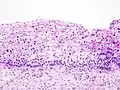

Histología

Los cambios microscópicos iniciales que corresponden al desarrollo de una neoplasia cervical intraepitelial son las displasias del epitelio, es decir, la superficie que recubre el cuello uterino, lo cual es indetectable y asintomático en la mujer.[2]

Los NIC tienen tres grados distintivos, basados en el espesor de la invasión por parte de las células escamosas:

- NIC1 (Grado I), es el tipo de menor riesgo, representa sólo una displasia leve o crecimiento celular anormal[1] y es considerado una lesión escamosa intraepitelial de bajo grado.[3] Se caracteriza por estar confinado al 1/3 basal del epitelio cervical.

- NIC2 (Grado II), es considerado una lesión escamosa intraepitelial de alto grado[3] y representan una displasia moderada, confinada a los 2/3 basales del epitelio cervical.

- NIC3 (Grado III): en este tipo de lesión, considerada también de alto grado, la displasia es severa y cubre más de los 2/3 de todo el epitelio cervical, en algunos casos incluyendo todo el grosor del revestimiento cervical. Esta lesión es considerada como un carcinoma in situ.